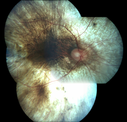

36 year old with vision loss for 14 years - Brother with choroideremia - Positive gene test. 20/80 OD and 20/160 OS

Choroideremia - Complete CHM gene deletion453 viewsVision loss since age 20 - now age 36 VA 20/160 (about) OU00000